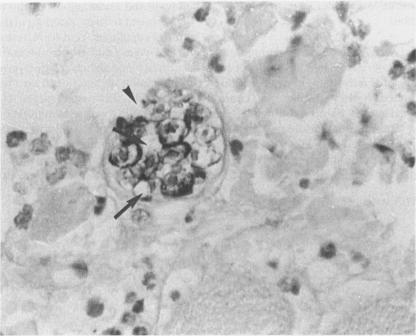

The degenerative and regenerative changes in murine skeletal muscle after injection of Bothrops asper venom were studied by histological, lectin histochemical and immunocytochemical techniques. According to our observations, the process was divided into four main stages: (a) During the first 3 days prominent degenerative events took place in skeletal muscle fibres, capillaries, arteries, veins and intramuscular nerves. An inflammatory infiltrate was abundant after the first day and removal of necrotic material was well advanced by the third day. (b) Muscle regeneration was evident by the fourth day. From 4 to 6 days there were two populations of regenerating muscle fibres, one of apparently normal fibres located in areas where capillary vessels were abundant, and another population of groups of regenerative fibres showing signs of degeneration. This second type of fibre was predominant in areas where the number of capillaries was greatly reduced. (c) One and 2 weeks after envenomation areas of small regenerative fibres of normal morphology and areas of degenerating regenerative fibres were observed. The latter were abundant in regions of dense fibrotic tissue and scarce capillaries. (d) Finally, at 4 and 8 weeks after envenomation there were both areas of fibrosis and areas where regenerating muscle fibres predominated. However, the diameter of these fibres was abnormally small, an indication that they may have been atrophic fibres. It is suggested that muscle regeneration is partially impaired after myonecrosis induced by Bothrops asper venom, probably due to the damage induced by this venom on muscle microvasculature and nerves.

通过组织学、凝集素组织化学和免疫细胞化学技术研究了注射矛头蝮蛇毒后小鼠骨骼肌的退行性和再生性变化。根据我们的观察,该过程分为四个主要阶段:(a) 在最初3天,骨骼肌纤维、毛细血管、动脉、静脉和肌内神经发生明显的退行性变化。第一天后炎症浸润丰富,到第三天坏死物质的清除进展良好。(b) 到第四天肌肉再生明显。在4至6天,有两类再生肌纤维,一类是明显正常的纤维,位于毛细血管丰富的区域,另一类是显示退变迹象的再生纤维群。后一种类型的纤维在毛细血管数量大大减少的区域占主导。(c) 注毒后1周和2周,观察到形态正常的小再生纤维区域和退变的再生纤维区域。后者在致密纤维化组织和毛细血管稀少的区域丰富。(d) 最后,在注毒后4周和8周,既有纤维化区域,也有再生肌纤维占主导的区域。然而,这些纤维的直径异常小,表明它们可能是萎缩纤维。有人提出,矛头蝮蛇毒诱导的肌坏死后肌肉再生部分受损,可能是由于这种毒液对肌肉微血管和神经造成的损害。